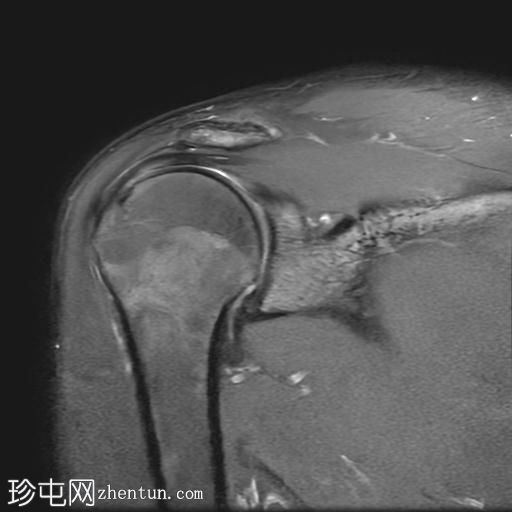

右肩外伤。

年龄:25岁

性别:男

MRI

冠状位

T2加权像

Bankart损伤伴前盂唇及下方骨髓水肿

Hill-Sachs缺损表现为骨性压陷,肱骨头后外侧及下方骨髓水肿/挫伤

冈上肌腱关键区纤维肌腱病

MRI结果符合肩关节前脱位伴Hill-Sachs缺损和Bankart损伤的

影像

学表现。